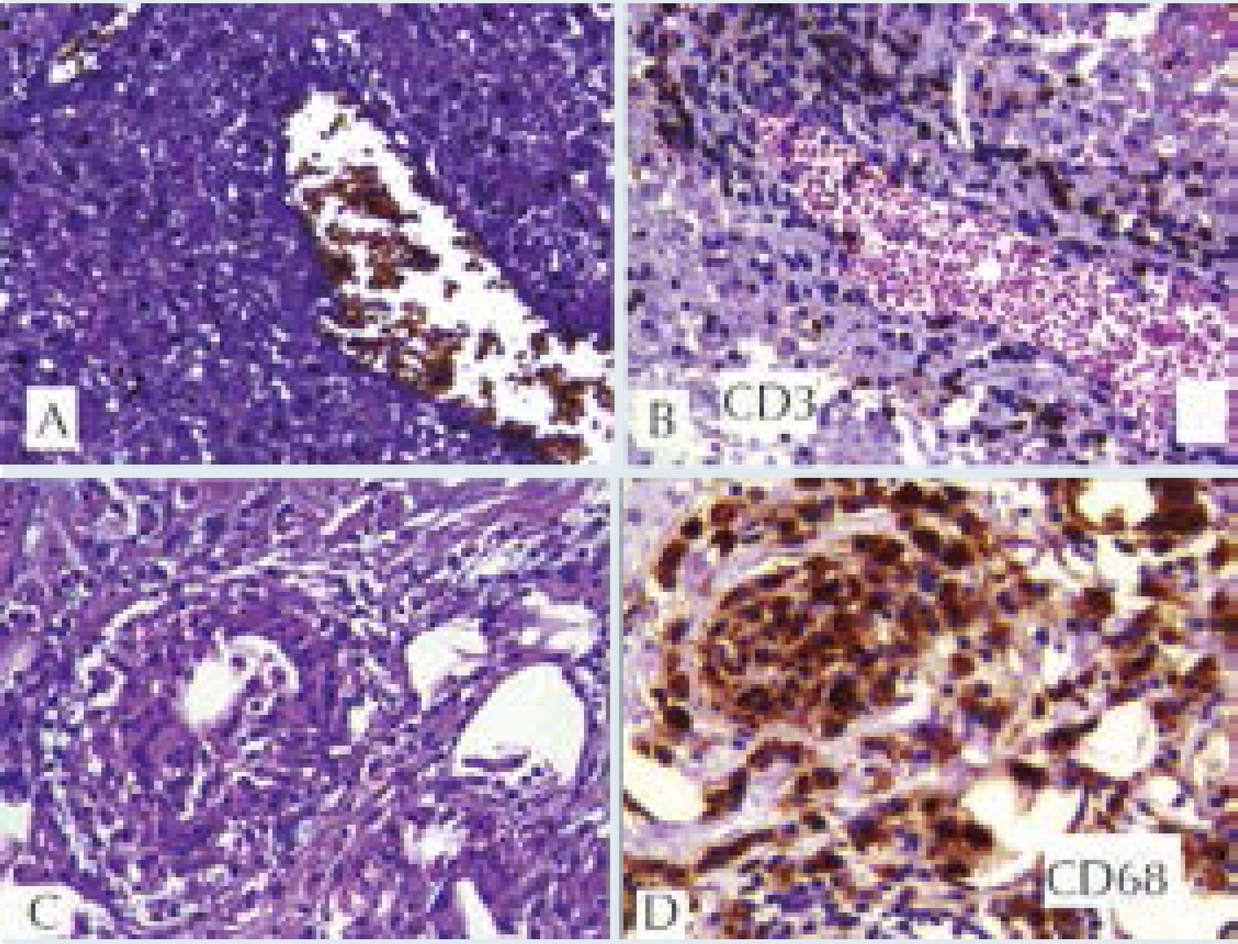

La ultrasonografía ocular reportó una lesión heterogénea que ejercía compresión y desplazamiento en sentido anterior del globo ocular derecho, y datos de inflamación de tejidos blandos (Figura 1). La tomografía computada describió la lesión como heterogénea e identificó datos de sinusitis y proptosis (Figura 2). Por resonancia magnética se reportó la misma lesión con aspecto heterogéneo de 5.5 ' 2.5 cm en sus diámetros mayores, que involucró tejidos musculares y con efecto de masa sobre estructuras orbitarias. No se observó extensión intracraneal, a cavidades paranasales ni al seno cavernoso (Figura 3). Ante una proptosis de rápida evolución y sospecha de probable rabdomiosarcoma se realizó biopsia transconjuntival de lesión intraconal y tejido peri-orbitario. Las preparaciones histológicas de la lesión intraconal y de la grasa orbitaria mostraron tejidos blandos con un proceso inflamatorio, necrótico con vasculitis de vasos de pequeño calibre con afección ocasional a vasos arteriales y venosos de mayor calibre. La vasculitis fue a expensas de linfocitos e histiocitos con trombosis aislada y algunos granulomas mal constituidos. El proceso inflamatorio estaba constituido por linfocitos, histiocitos, células plasmáticas y en una zona se mezclan con numerosos neutrófilos con cariorexis; la necrosis fue isquémica. Se realizaron diversas tinciones de histoquímica convencional e inmunohistoquímica para descartar neoplasia linfoide maligna o proceso infeccioso granulomatoso como micobacterias u hongos. La glándula lagrimal mostró afección por el proceso inflamatorio, la necrosis isquémica y la propia vasculitis. El diagnóstico fue de: granulomatosis de Wegener (Figura 4).

Figura 4 Biopsia de tejido periorbitario. A) Vasculitis: tinción de fibras elásticas en vaso venoso con infiltrado linfocitario en su pared. B) CD3 marcador de linfocitos T en la pared de la vena. C) Granuloma constituido por histiocitos epitelioides y una célula gigante multinucleada. D) CD68 marcador de histiocitos positivo en granuloma. A-C) Tinción de hematoxilina & eosina a 40X. D) Tinción para inmunoperoxidasa a 40X.